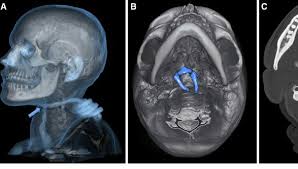

É a aplicação das técnicas de imagem médica — como radiografia, tomografia e até ressonância — no contexto legal e criminal. Com ela, é possível analisar traumas, balísticas, identificar corpos e reconstruir eventos ligados à causa da morte ou ferimentos.

- ✔️ Localização de projéteis e objetos metálicos

- Solução de crimes com auxílio de reconstruções tomográficas